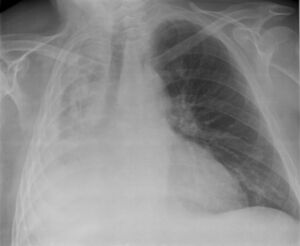

همود في الرئة اليمنى لمريض.

همود الرئة في الفص الأيمن السفلي كما يظهر بالأشعة السينية على الصدر.

• الأشعة السينية للصدر (الانخماص ما بعد العمليات الجراحية يظهر في الجزء الأدنى من الرئتين)